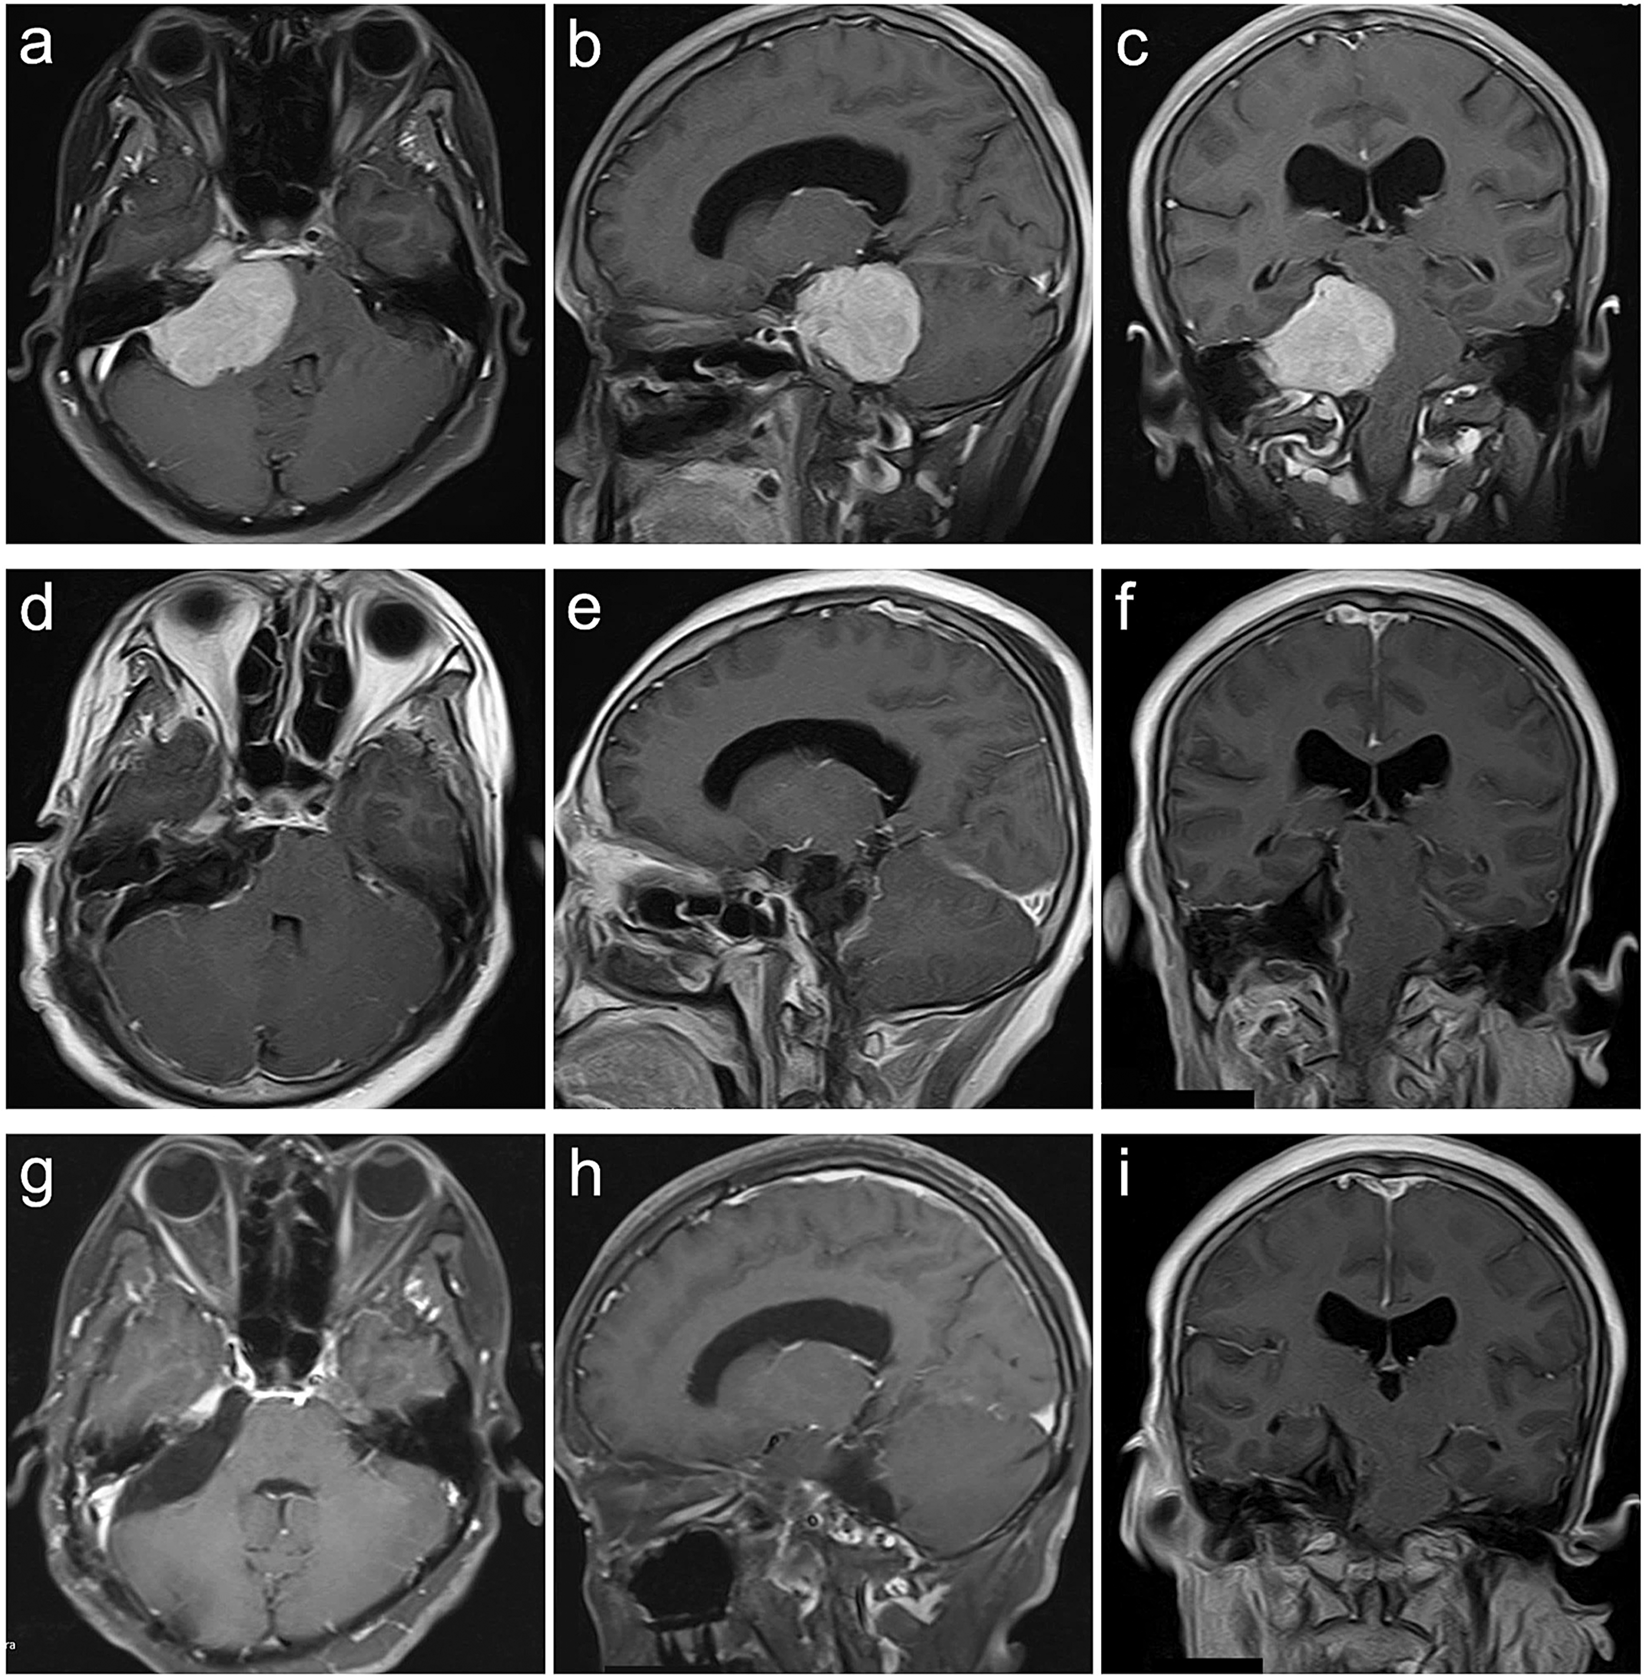

Figure 3

Petroclival type case. A 47-year-old female presented with headache, dysphagia, bucking, hearing impairment and ataxia for 36 months. The preoperative KPS score was 60. She was achieved GTR with the RTTA of palsy in CN V VI,VI and VII and gastric intubation. The postoperative KPS score was 50. With a follow-up of 24 months, she participated in normal activities and had a KPS score of 80 without recurrence. (a–c) Preoperative MRI T1 contrast axial, sagittal, and coronal images. (d–f) Postoperative MRI T1 contrast axial, sagittal, and coronal images. (g–i) Follow-up MRI T1 contrast axial, sagittal, and coronal images.